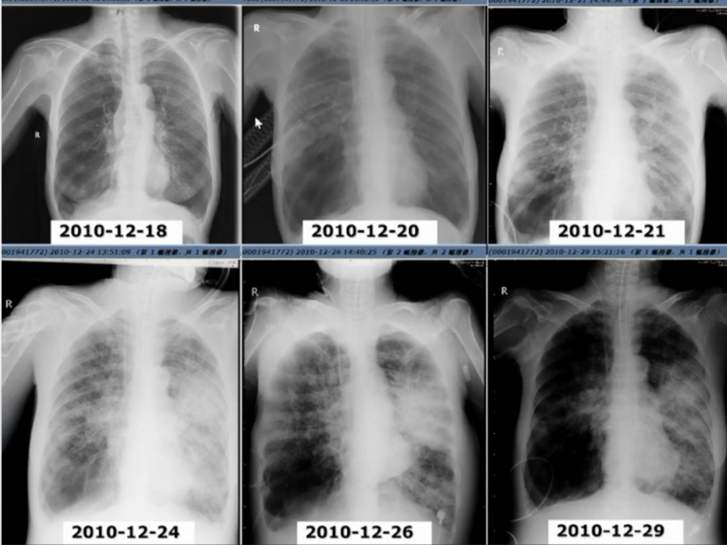

70岁女性COPD患者,反复咳嗽、咳痰10年,喘憋2年,加重12天,于2010年12月20日15时入住RICU。入院前,患者在外院使用了广谱抗生素和激素治疗,但病情未缓解,因患者呼吸衰竭急性加重插管入ICU。

入科诊断为AECOPD,Ⅱ型呼吸衰竭,肺源性心脏病,2型糖尿病,急性肾功能不全。患者入院时,急诊胸部CT可见其双肺肺气肿表现,12月20日,急诊插管上呼吸机后,在肺内仍未见明确的斑片渗出影。12月20—21日行气管镜检查,气管镜下可见左肺各叶段支气管黏膜充血水肿、分泌物填充伴伪膜形成,随后患者左肺逐渐出现斑片渗出影,并逐渐加重,患者同时出现急性肾衰竭和消化道出血,以及神志障碍和休克。气管镜下留取黏膜组织标本可见真菌菌丝侵袭气道黏膜局部,引起感染。积极给予两性霉素B和伏立康唑抗感染治疗,但患者最终因多脏器功能衰竭而死亡。

图片

回顾该病例的救治过程:住院第2天行气管镜检查,可见大量的黏稠痰液,吸痰后可见局部黏膜充血,间嵴水肿,有伪膜和白斑。病理检查发现黏膜中大量菌丝侵袭至黏膜内。影像学检查提示COPD患者出现急性加重时,肺内并无明确病变,随着病情进展,曲霉菌感染从气道内逐渐向肺实质播散。当机体免疫功能受到抑制时,曲霉菌会进一步向肺实质播散,并引起严重的自身免疫相关损伤,最终导致多脏器功能衰竭,预后不良。早期启动抗真菌治疗的疗效尚可。当进展至IPA时,即使采用联合治疗,预后可能也不容乐观。